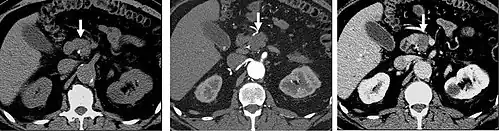

Kidney masses

Detection and characterization of renal parenchymal masses is a frequent indication for CT. An initial noncontrast CT is important for detecting calcium or fat in a lesion, and to provide baseline attenuation of any renal masses. Following noncontrast scanning, intravenous contrast is injected and a corticomedullary phase is obtained at approximately 70 seconds (figure 7a, 7b). The corticomedullary phase is characterized by enhancement of the renal cortex as well as the renal vasculature. This phase is valuable in the evaluation of benign renal variants, lymphadenopathy and vasculature, however certain medullary renal masses may not be visible during this phase due to minimal enhancement of the medulla and collecting system. The parenchymal phase is obtained approximately 100–200 seconds after the injection of contrast material (figure 7c). Parenchymal phase imaging demonstrates continued enhancement of the cortex, enhancement of the medulla, and various levels of contrast material in the collecting system. The parenchymal phase is highly important for the detection and characterization of renal masses, parenchymal abnormalities, and the renal collecting system. This method of imaging does not evaluate for abnormalities of the collecting system.

Common renal masses can occasionally be differentiated from each other using this imaging technique. Renal cell carcinomas and oncocytomas typically demonstrate intense heterogeneous enhancement on the parenchymal phase images and cannot be reliably differentiated from each other but can be distinguished from other renal masses. Angiomyolipomas (AML's) also demonstrate intense contrast enhancement but characteristically contain macroscopic fat which can be detected on the noncontrast images, and can help to differentiate AML's from renal cell carcinomas and oncocytomas. Renal lymphoma on the other hand, will often have decreased enhancement when compared to the renal parenchyma on the parenchymal phase images.

-

FIGURE 7. Selected images from a renal mass specific protocol CT. Corticomedullary phase (axial 7a) demonstrates peripheral enhancement of the renal cortex with minimal opacification of the renal medulla. There is a large renal cell carcinoma in the left kidney (right in image) which can be differentiated from the normal renal parenchyma by the heterogeneous and differential enhancement. The renal artery and vein are opacified in this phase as well. The collecting system is not opacified (coronal reformat 7b). In the parenchymal phase, the renal cortex and the medulla are enhancing. The renal cell carcinoma in the left kidney is not as well defined when compared to the corticomedullary phase images, but is actually slightly more conspicuous. There is some contrast noted within the collecting system during this phase (7c).